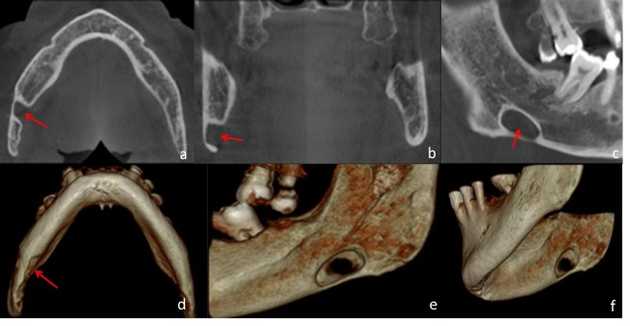

Paciente femenino de 51 años de edad, quien acudió a la consulta para evaluación del reborde alveolar previo a la colocación de implantes dentales. A la evaluación de la radiografía panorámica (Figura 3) se evidenció una imagen radiolúcida de límites definidos, bordes corticalizados, de forma ovoide, localizada en el cuerpo mandibular izquierdo, proxima a la basal mandibular, y proyectada sobre el canal mandibular. En el estudio por TCHC se observó en los cortes coronal y axial, una concavidad bien delimitada, formada a expensas de la tabla ósea lingual (Figura 4a-b). En el corte sagital (Figura 4c) y reconstrucciones 3D (Figura 4d-e) se evidenció la imagen hipodensa bien delimitada en la región antegonial, sin compromiso de la base de la mandíbula o el canal mandibular. La imagen muestró signos tomográficos compatibles con COS Tipo I.

Figura 3 FIGURA 3. Radiografía panorámica se observa en mandíbula del lado izquierdo imagen radiolúcida de forma ovoide, limites definidos, proyectada sobre el canal mandibular, localizada en región antegonial (Flechas rojas)